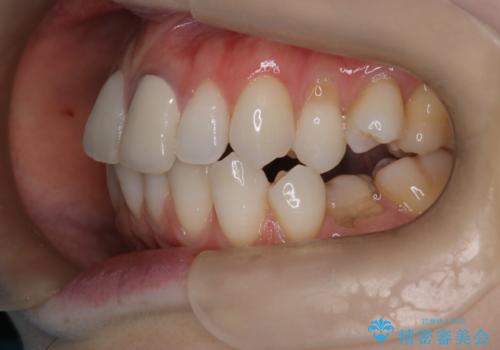

- 患者様は、歯並びの乱れ(叢生)を整えたいが、前歯の突出感は気にならないとのことで来院されました。診察の結果、全体的な歯列のスペース不足により抜歯が必要と判断。しかし、前歯を大きく下げる必要はなかったため、小臼歯の中でも5番(第二小臼歯)を抜歯する治療計画を立てました。装置は、上顎が舌側(リンガル)、下顎が表側(審美ワイヤー)のハーフリンガル矯正を採用し、目立ちにくさと効率的な歯の移動を両立しました。

抜歯によって歯を並べるためのスペースを確保。その後、ハーフリンガル矯正を用いて、上顎は舌側から、下顎は目立ちにくいワイヤーで歯を誘導し、歯列全体を整えました。治療期間を通じて、噛み合わせのバランスも改善し、機能的にも審美的にも理想的な仕上がりとなりました。患者様からは「目立たずに矯正でき、きれいな歯並びになって嬉しい」とご満足いただきました。